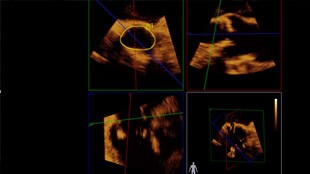

Your patient has been diagnosed with symptomatic aortic stenosis. She’s 85 years old, has diabetes and high blood pressure. You know she’s high risk and not a fit for cardiac surgery, but she may be a candidate for transcatheter aortic valve replacement (TAVR). Today, innovative imaging solutions and percutaneous devices are offering hope for some patients who, up until now, have had no other options.